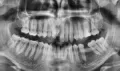

Мне 24 года, главная моя проблема — это выпирающие вперед верхние боковые резцы, а первые резцы с задней стороны полностью забломбированы на штифтах. Каким образом мне можно исправить кривизну передних верхних зубов? Носить брекеты желания нет.

Здравствуйте. Подскажите, возможно ли выровнять зубы (кривые только верхняя челюсть) без брекетов? У меня торчат 2 зуба вверху. Можно ли их сточить и наростить искуственные?